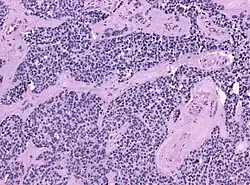

Nach neueren molekularbiologischen Forschungsergebnissen bildet sich das Malignom wahrscheinlich aus einer entarteten olfaktorischen Stammzelle. Von anderen Malignomen dieser Region wie Karzinomen, Sarkomen und Lymphomen unterscheidet sich das Ästhesioneuroblastom schon in der lichtmikroskopischen Betrachtung; der Nachweis gelingt mit immunhistochemisch darstellbaren Zellstrukturen (S-100, NSE positiv; Zytokeratin, Vimentin negativ).